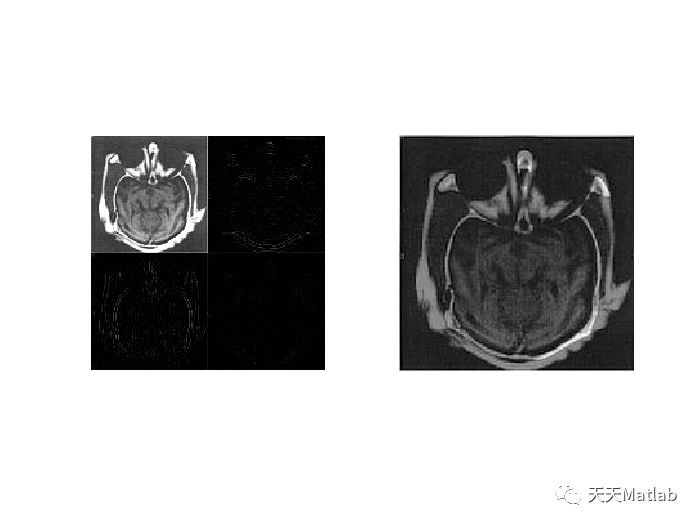

clearx1=imread('ct.jpg');subplot(221);imshow(x1);title('ct图像');x2=imread('mri.jpg');subplot(222);imshow(x2);title('mri图像');X1=double(x1);X2=double(x2);%将两幅图像进行一级db4小波变换[ca1,ch1,cv1,cd1]=dwt2(X1,'db4');subplot(223);b1=uint8([ca1 ch1;cv1 cd1]);imshow(b1);title('ct图像一级db4小波分解');[ca2,ch2,cv2,cd2]=dwt2(X2,'db4');subplot(224);b2=uint8([ca2 ch2;cv2 cd2]);imshow(b2);title('mri图像一级db4小波分解');%按照一定融合规则进行融合ca=dipinchuli(ca1,ca2);ch=PCAfusion(ch1,ch2);cv=PCAfusion(cv1,cv2);cd=PCAfusion(cd1,cd2);figure;subplot(121);imshow(uint8([ca ch;cv cd]));title('融合后小波系数');X=idwt2(ca,ch,cv,cd,'db4');subplot(122);imshow(uint8(X));title('融合后重构图像');

3 仿真结果